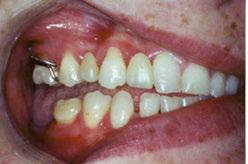

Figure 3: Initial right buccal

This case involves a 13-year-old female patient with a complex malocclusion that includes multiple dental and skeletal issues. During the initial consultation, clinical evaluation showed severe maxillary crowding along with generalized spacing in the mandibular arch. The patient’s occlusal relationships were asymmetric, with a Class I molar relationship on the right side and a Class II molar relationship on the left. Notably, an anterior crossbite was observed, further complicated by a narrow, V-shaped maxillary arch — a common presentation that often exacerbates anterior-posterior discrepancies and limits functional occlusion. The patient also demonstrated poor oral hygiene, which is a key indicator of an indirect bonding system that does not reduce excess flash. ODB is superior in flash reduction, by being able to remove excess adhesive from three sides of the bracket instead of competitors who only remove adhesive from one side of the bracket. The presence of adhesive around brackets contributes to surface roughness which leads to plaque accumulation.1 Flash reduction will be very important for every patient’s orthodontic success (Figures 1-3).